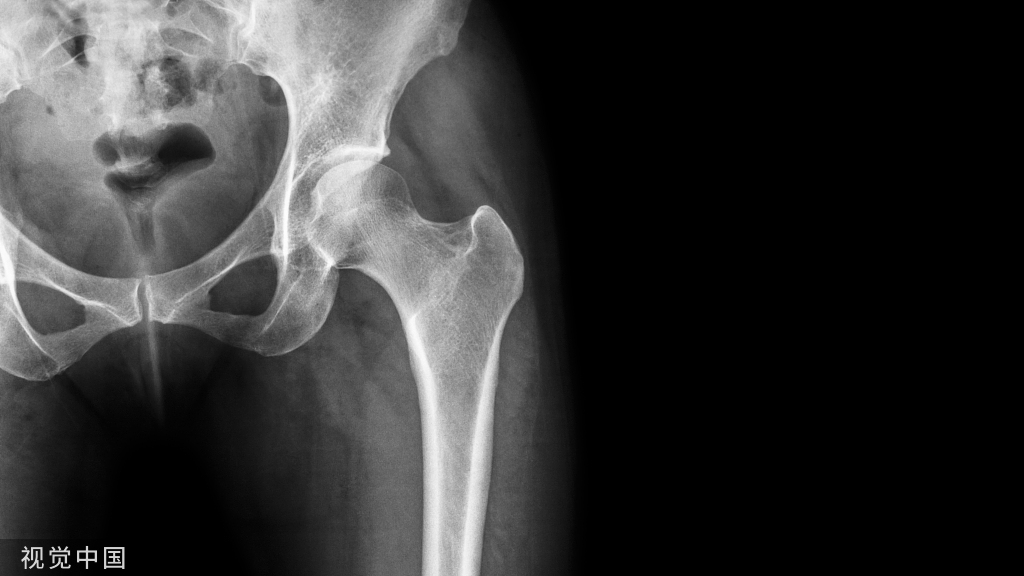

19 世纪末,随着 X 线的临床运用,骨折的诊断、整复、手术固定及术后观察有极大提高,使骨科学得到长足发展。

1950年,John Charnley 确立了人工关节低摩擦理论,提出并设计“金属-聚乙烯”全髋关节置换术假体,被誉为“现代人工髋关节置换之父”。